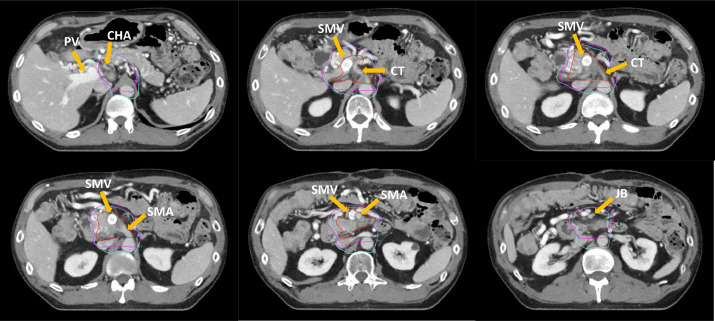

Hình 2. Các hình ảnh cắt ngang minh hoạ một kế hoạch xạ trị. GTV (Đỏ), CTV dự phòng, thể tích tam giác (Xanh biển nhạt). Một thể tích bia lâm sàng dự phòng dựa trên atlat NRG GI011 để so sánh.